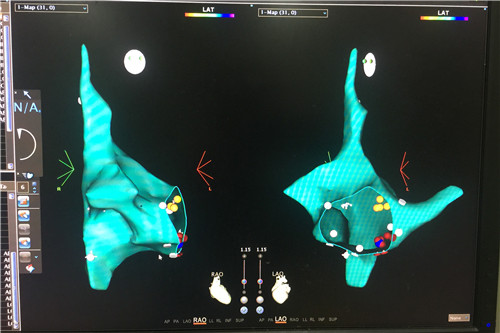

以前常规的射频消融手术都是在X射线下进行的,医生和患者不仅要长时间暴露在X射线的照射下,带来健康隐患,而且存在消融靶点定位准确性不高,有一定复发的可能性。CARTO系统特别是CARTO3是近年来心律失常治疗领域的革命性技术,专门用于治疗房颤、室上速、室速和室性早搏等心律失常。该系统能将患者心脏的三维立体解剖图像和电传导信息准确清晰地显示在电脑屏幕上,指导操作医生快速准确地找到靶点,将其消融消灭,不仅提高了手术成功率,也显著降低了并发症发生的危险性以及心律失常的复发。

虽然CARTO技术已经开展几年了,但是目前能成功运用该技术的医院并不多,特别是地市级医院。该技术在心内科多次成功的运用,使得临床医学院/附属医院导管射频消融治疗心律失常的成功率和安全性大幅提升,标志着临床医学院/附属医院心内科心律失常介入治疗又上了一个新台阶。